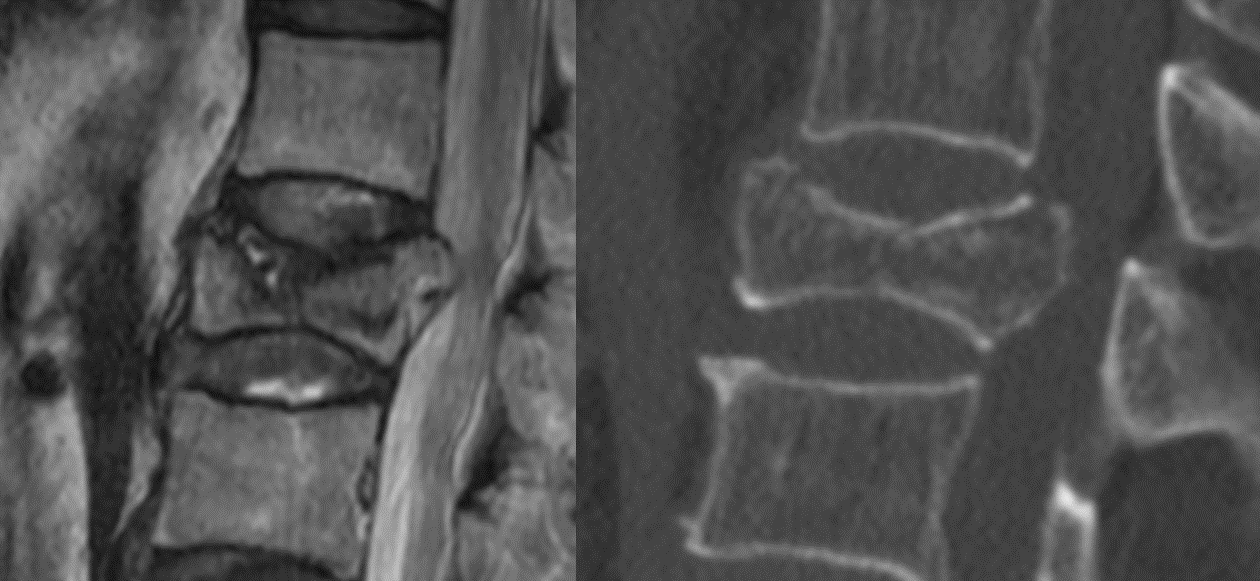

압박 골절

압박 골절은 척추뼈가 압박되면서 발생하는 골절을 의미합니다. 이는 50세 이상의 여성에게 더 흔합니다. 나이와 골다공증으로 인해 뼈가 약해지기 때문에 뼈가 부러질 가능성이 더 높습니다. 시간이 지남에 따라 척추뼈가 부러지면 척추가 무너지고 구부러지게 됩니다. 치료에는 휴식, 약물 치료, 교정기 및 최소 침습 수술이 포함됩니다.

골절은 각 척추뼈 앞쪽의 두껍고 둥근 부분인 척추체에서 발생합니다. 뼈의 골절로 인해 척추가 약해지고 붕괴됩니다. 시간이 지남에 따라 이러한 골절은 자세에 영향을 미칩니다. 척추가 앞으로 휘어지고 사람이 "구부러진" 것처럼 보입니다(후만증).

압박 골절은 일반적으로 척추의 흉부(중간) 부분, 특히 하부 흉부 부위에서 발생합니다. 골다공증으로 인해 발생하는 경우가 많습니다. 그러나 외상(예: 자동차 충돌) 이후나 척추 종양으로 인해 발생할 수도 있습니다.